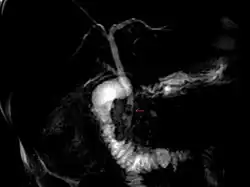

Magnetic resonance cholangiopancreatography (MRCP) image of two gallstones in the distal common bile duct

The diagnosis of choledocholithiasis is suggested when the liver function blood test shows an elevation in bilirubin and serum transaminases. Other indicators include raised indicators of ampulla of vater (pancreatic duct obstruction) such as lipases and amylases. In prolonged cases the international normalized ratio (INR) may change due to a decrease in vitamin K absorption. (It is the decreased bile flow which reduces fat breakdown and therefore absorption of fat soluble vitamins). The diagnosis is confirmed with either a magnetic resonance cholangiopancreatography (MRCP), an endoscopic retrograde cholangiopancreatography (ERCP), or an intraoperative cholangiogram. If the patient must have the gallbladder removed for gallstones, the surgeon may choose to proceed with the surgery, and obtain a cholangiogram during the surgery. If the cholangiogram shows a stone in the bile duct, the surgeon may attempt to treat the problem by flushing the stone into the intestine or retrieve the stone back through the cystic duct.